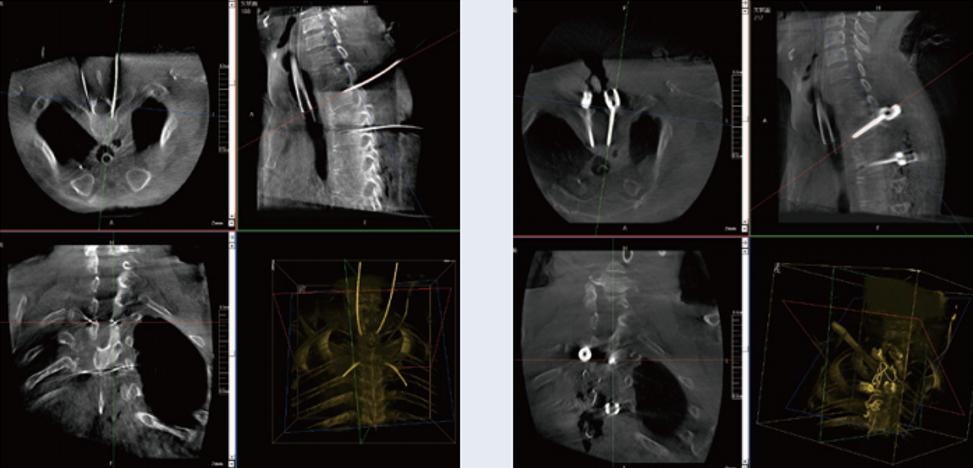

螺钉规划后的图像

植入螺钉后的图像

术中三维C臂与骨科导航机器人配合应用,实现准确定位,确保了手术安全、高效完成。术后二维、三维影像显示手术效果良好,达到预期目的。

普爱医疗三维C臂提供了高质量的术中实时三维图像数据,保障了骨科导航机器人手术的准确度和安全性,取得不错的手术效果。同时,三维C臂特有的断层成像,能帮助医生在术中非常直观地判断螺钉植入的准确度。